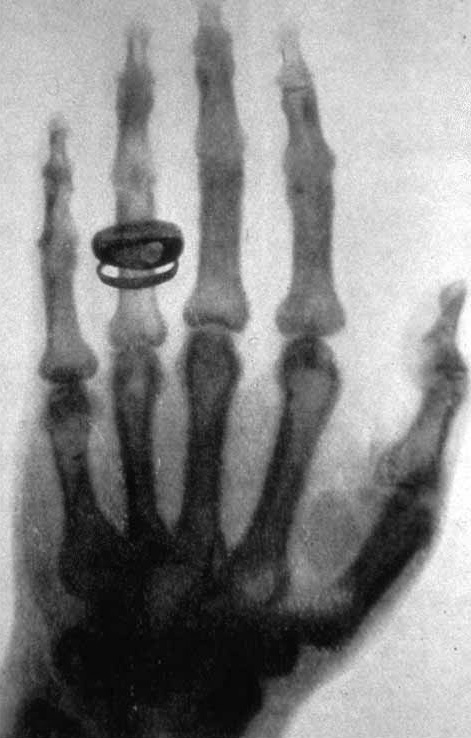

Röntgen explora la imatge obtinguda en posar la mà de la seva dona entre el tub i la pantalla, i observa que el que es veu és l’esquelet de la mà, com si la carn hagués desaparegut (Fig.2).